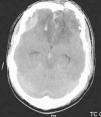

Paciente de 17 años sin antecedentes de interés que ingresa en la UCIP de nuestro centro por TCE grave tras precipitación desde 12 metros de altura en contexto de intoxicación etílica. Glasgow inicial de 3 que requiere intubación en el lugar del accidente. A su llegada a nuestro centro presenta hipotensión refractaria a expansores de volumen que requiere soporte inotrópico con dopamina y adrenalina. En la exploración destaca midriasis arreactiva izquierda por lo que se administran 100ml de suero salino hipertónico al 6%. En la analítica destaca hematocrito de 31,9%, discreta acidosis metabólica (pH 7,28, pCO2 44,6, Bic 20,5, EB −5,1), hipernatremia de 156mmol/l, lactato de 4,1mmol/l y CPK de 3.887UI/l. Se realiza body-TC que muestra fractura de macizo facial y base de cráneo, pequeño hematoma epidural frontotemporal derecho, contusiones frontales y edema cerebral. Presenta además fractura estable de varios cuerpos vertebrales y contusión pulmonar bilateral con hemoneumotórax izquierdo que precisa drenaje. Se monitoriza presión intracraneal mediante sensor PIC y flujo sanguíneo cerebral mediante doppler, que se mantienen normales durante todo el ingreso. Se administra sedoanalgesia con mórfico y midazolam, profilaxis anticomicial con fenitoína y cobertura antibiótica con cefotaxima y vancomicina. A las 18h inicia hipertermia (hasta 40°C) que persiste durante 8h a pesar de medidas farmacológicas y físicas habituales. Posteriormente presenta poliuria compatible con diabetes insípida que se autolimita tras 2 dosis de desmopresina. Durante los siguientes días persiste hipernatremia (máximo 182mmol/l) de difícil control a pesar de minimizar aportes de sodio y optimizar hidratación. El sexto día de ingreso se objetiva en analítica de control un incremento de CPK hasta 36.000UI/l, iniciándose hiperhidratación (3.000ml/m2) y alcalinización de orina. El séptimo día de ingreso presenta convulsión tónico-clónica generalizada que cede espontáneamente en 30 segundos. Se realiza EEG que no muestra actividad paroxística. Se objetiva a partir de este momento salida de masa encefálica a través de fosas nasales. El octavo día de ingreso, ante el aumento progresivo de CPK (hasta 67.000UI/l) en el contexto de insuficiencia renal aguda (urea 102mg/dl, creatinina 1,39mg/dl, aclaramiento de creatinina 95ml/min/1,73m2) con diuresis conservada, se inicia hemodiafiltración venovenosa continua. Presenta mejoría progresiva con corrección de la hipernatremia y normalización de los niveles de CPK, pudiéndose retirar la depuración extrarrenal a las 72h de su inicio. Tras su estabilización el paciente fue trasladado a su país de origen donde debido a la gravedad de las lesiones cerebrales (fig. 1) se decidió realizar limitación del esfuerzo terapéutico y fue éxitus.